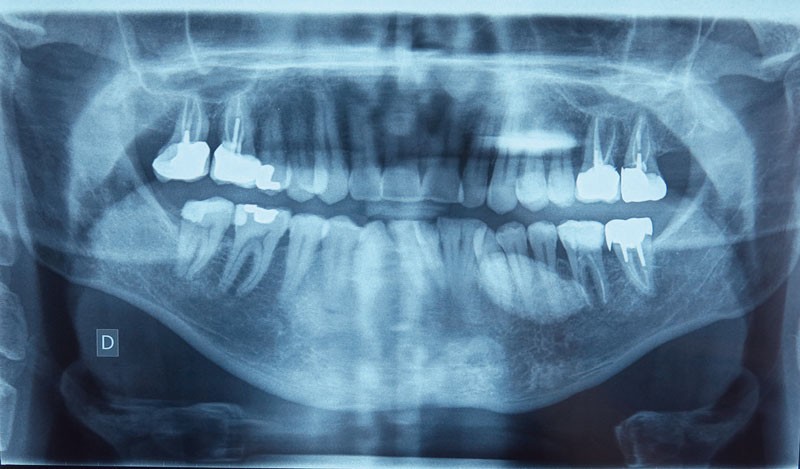

Une radiographie panoramique, une échographie de la loge submandibulaire gauche et un cliché occlusal permettent de compléter l’examen clinique.

Sur la première (fig. 2), on retrouve au niveau du secteur 3 une lésion radio-opaque de plusieurs centimètres, homogène, de forme arrondie aux contours bien délimités, et sans rapport avec les apex des dents présentes.